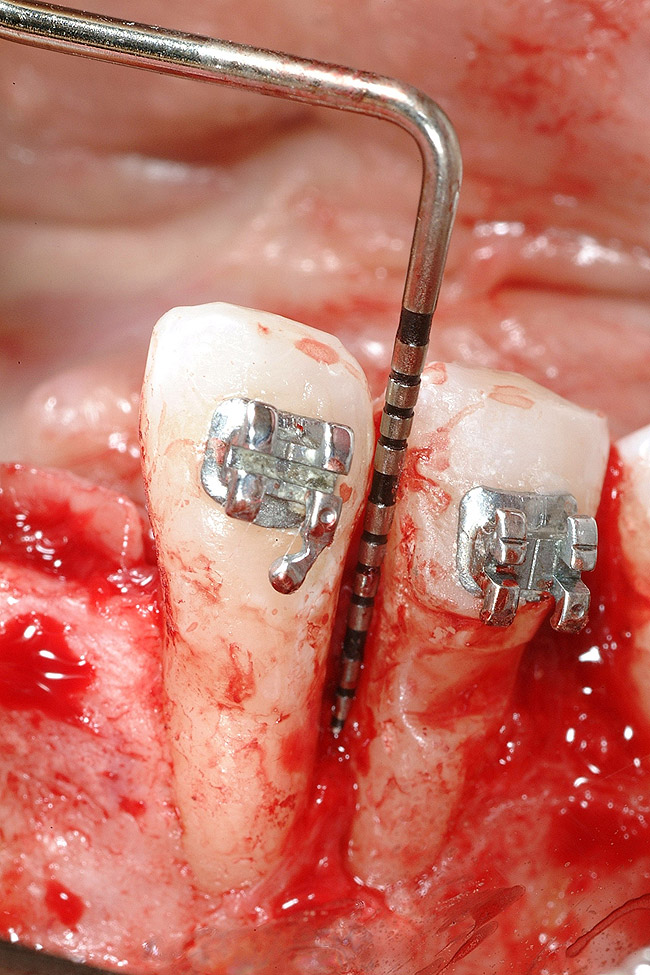

Figure 18  Implant placement with resulting facial dehiscence. Cortical perforations placed to promote angiogenesis.

Figure 18